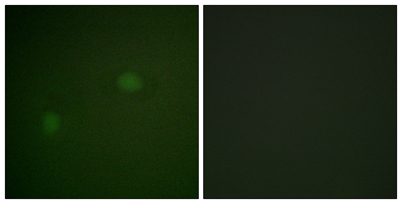

| Dilutions: | Western Blot: 1/500 - 1/2000. Immunohistochemistry: 1/100 - 1/300. Immunofluorescence: 1/200 - 1/1000. ELISA: 1/20000. Not yet tested in other applications. |

| Cellular localization: | Nucleus, nucleolus . Nucleus, nucleoplasm . Cytoplasm, cytoskeleton, microtubule organizing center, centrosome . Generally nucleolar, but is translocated to the nucleoplasm in case of serum starvation or treatment with anticancer drugs. Has been found in the cytoplasm in patients with primary acute myelogenous leukemia (AML), but not with secondary AML. Can shuttle between cytoplasm and nucleus. Co- localizes with the methylated form of RPS10 in the granular component (GC) region of the nucleolus. Colocalized with nucleolin and APEX1 in nucleoli. Isoform 1 of NEK2 is required for its localization to the centrosome during mitosis. |